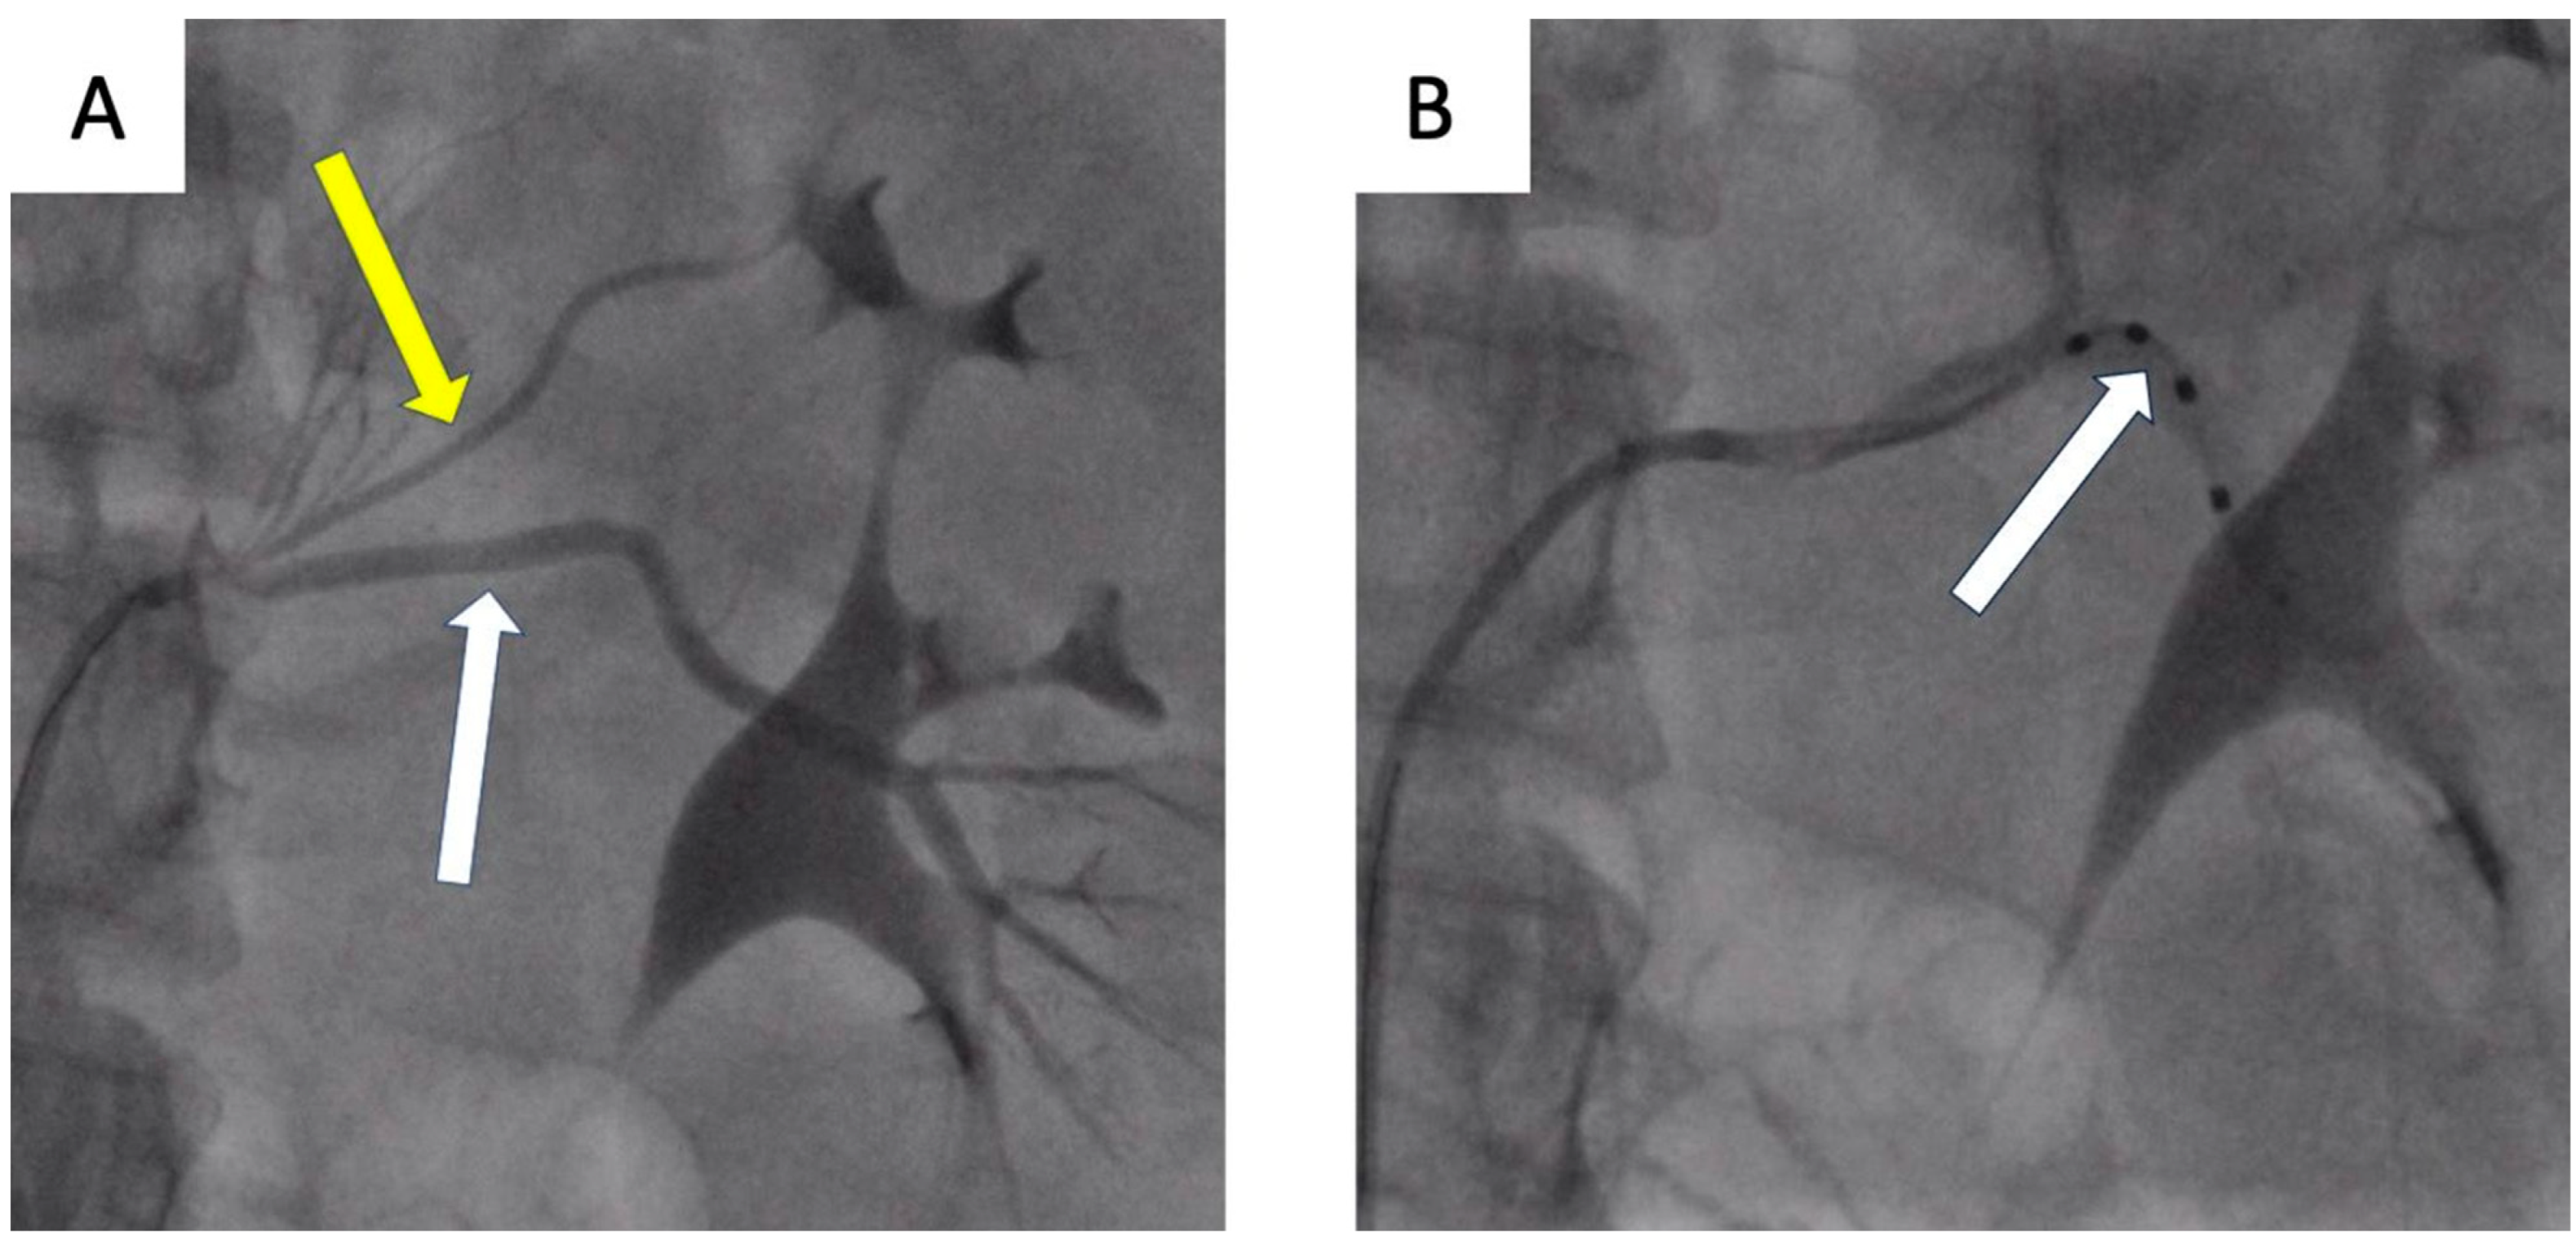

- Możeńska, O.; Rosiak, M.; Gziut, A.; Gil, R.J.; Kosior, D.A. First-in-man experience with renal denervation of multiple renal arteries in a patient with solitary kidney and resistant hypertension. Pol. Arch. Intern. Med. 2017, 127, 60–62. [Google Scholar] [CrossRef]

- Tokarek, T.; Rajtar-Salwa, R.; Rzeszutko, Ł.; Bartuś, S. Long-term benefit of redo sympathetic renal denervation in a patient with resistant hypertension. Postep. Kardiol. Inter. 2021, 17, 239–241. [Google Scholar] [CrossRef] [PubMed]

- Atas, H.; Durmus, E.; Sunbul, M.; Mutlu, B. Successful accessory renal artery denervation in a patient with resistant hypertension. Heart Views 2014, 15, 19–21. [Google Scholar] [PubMed]

- Bertoldi, L.; Latib, A.; Piraino, D.; Regazzoli, D.; Sticchi, A.; Pizzetti, G.; Camici, P.G.; Colombo, A. Renal denervation in a patient with two renal accessory arteries: A case report. Blood Press 2013, 22, 325–328. [Google Scholar] [CrossRef] [PubMed]